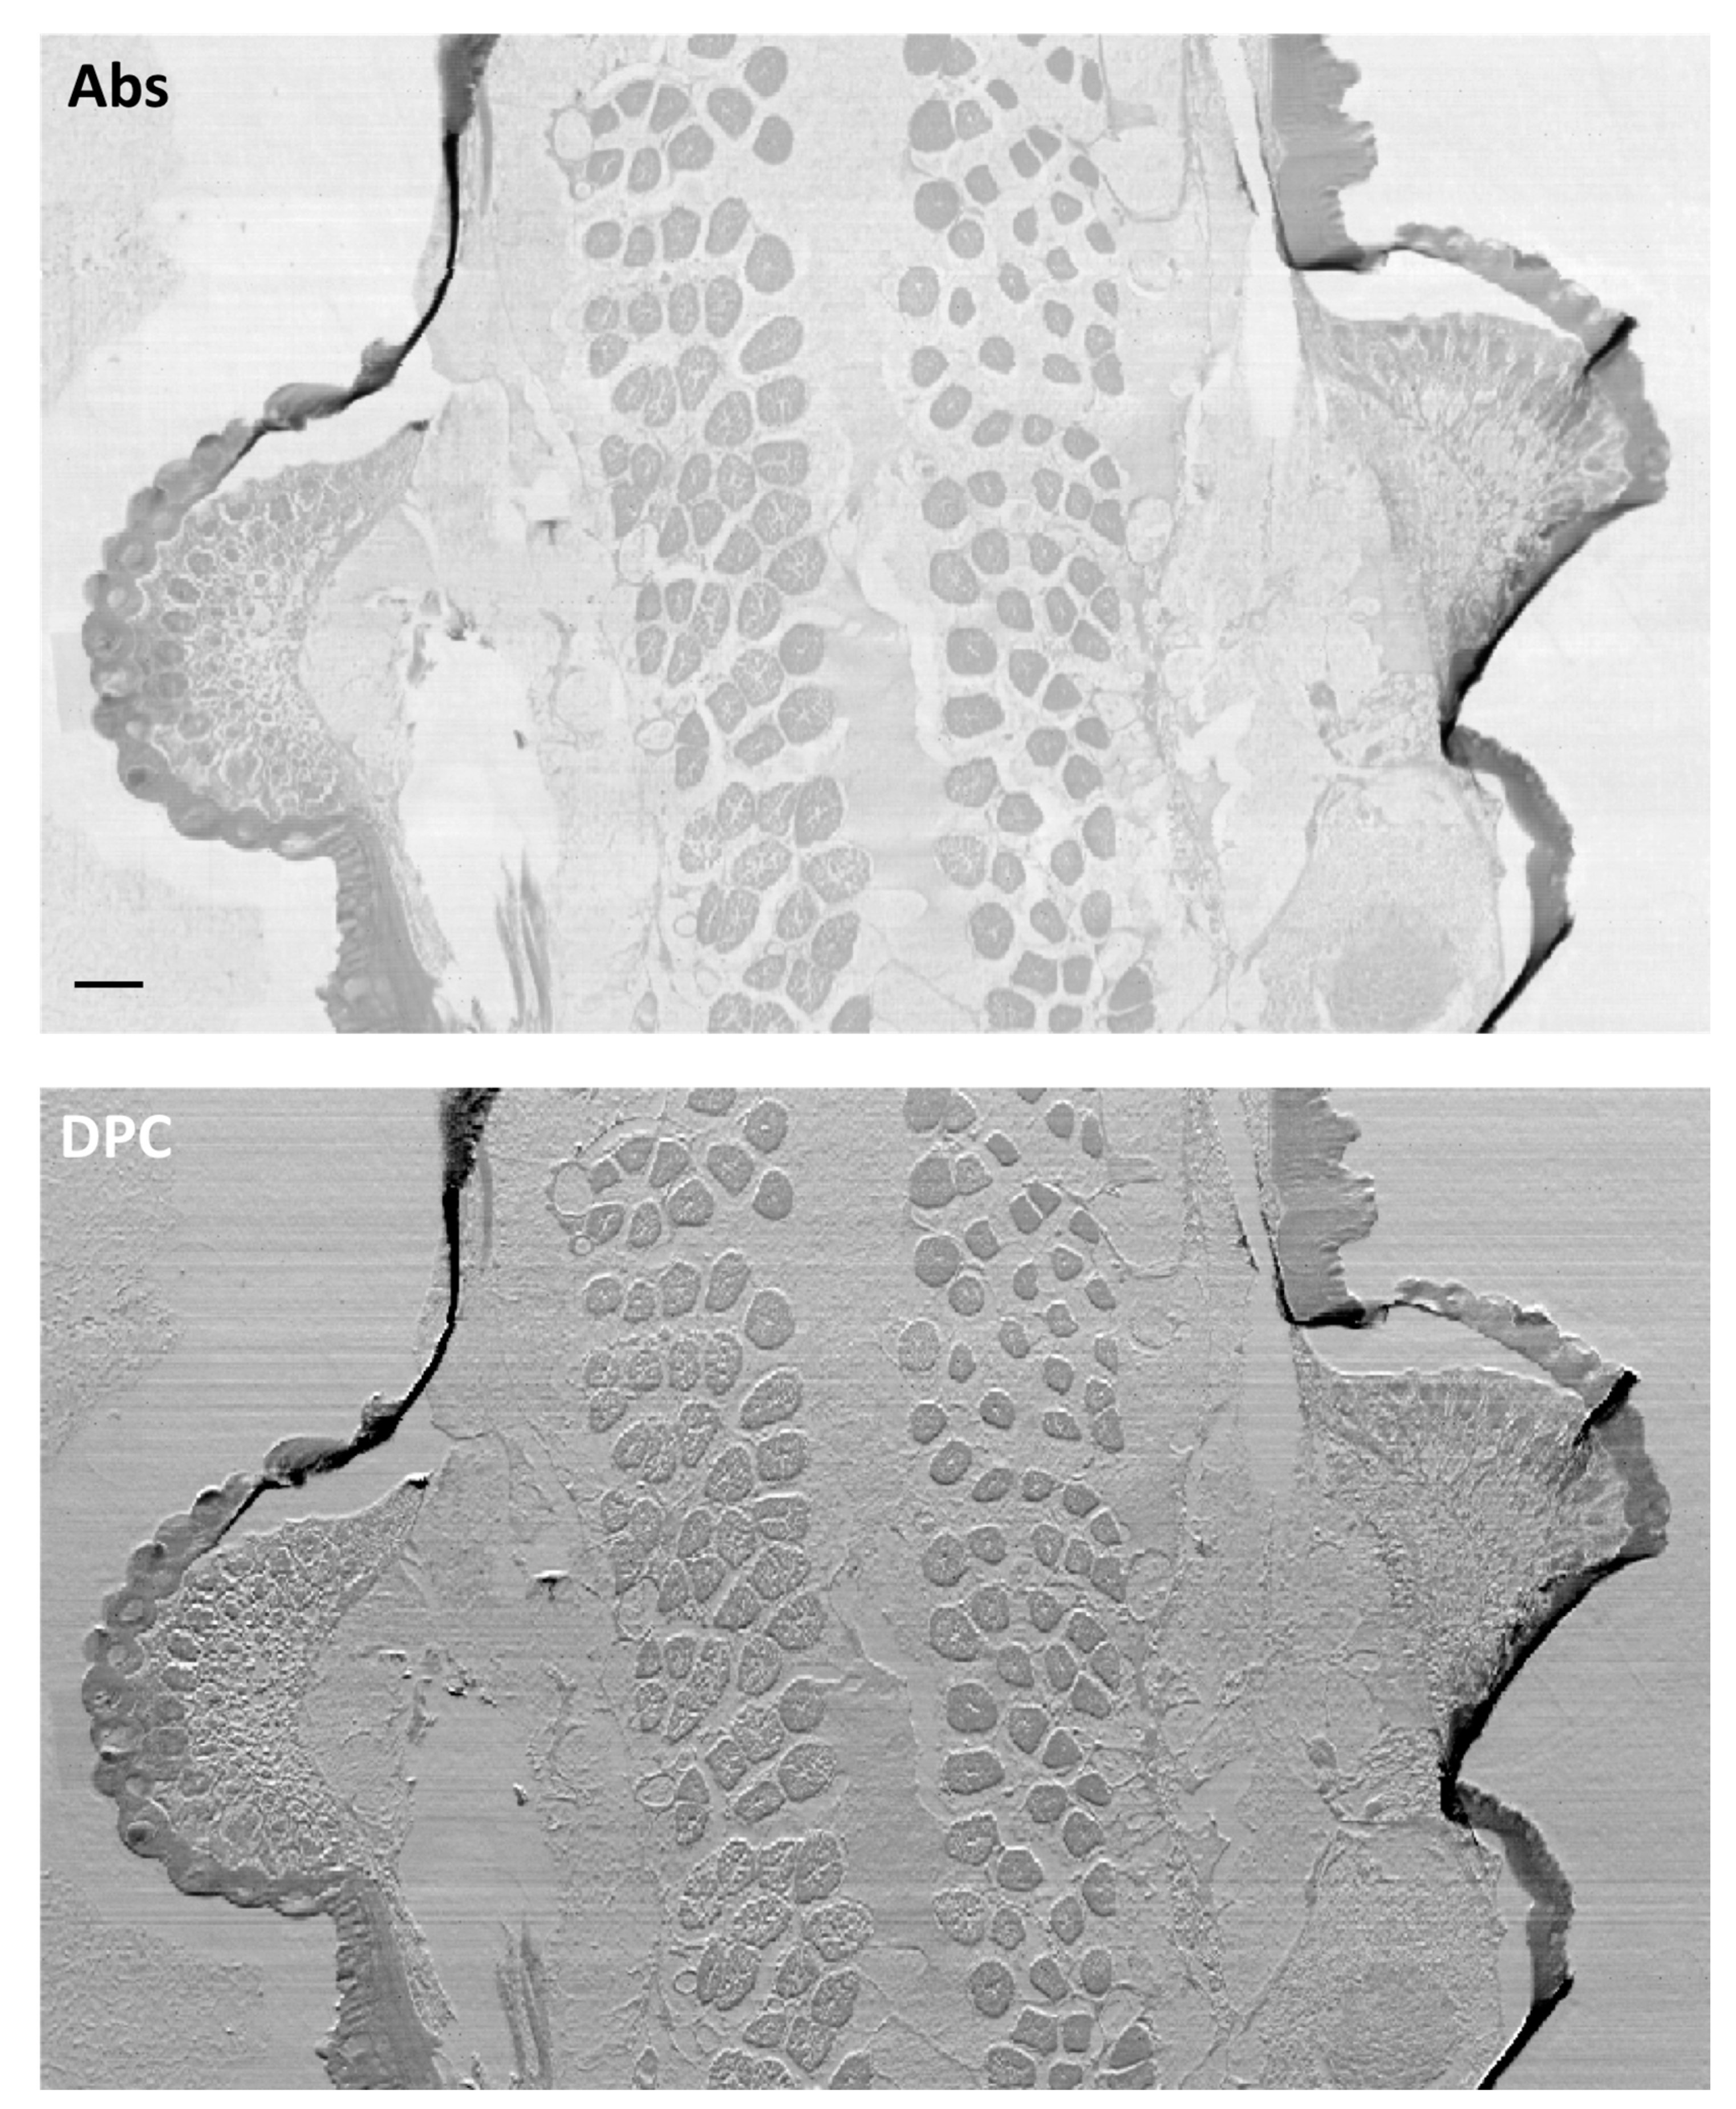

- Pascolo, L.; Sena, G.; Gianoncelli, A.; Cernogoraz, A.; Kourousias, G.; Metscher, B.D.; Romano, F.; Zito, G.; Pacilè, S.; Barroso, R.; et al. Hard and Soft X-ray Imaging to Resolve Human Ovarian Cortical Structures. J. Synchrotron Radiat. 2019, 26, 1322–1329. [Google Scholar] [CrossRef] [PubMed]

- Pascolo, L.; Venturin, I.; Gianoncelli, A.; Salomé, M.; Altissimo, M.; Bedolla, D.E.; Giolo, E.; Martinelli, M.; Luppi, S.; Romano, F.; et al. Morphological and Chemical Information in Fresh and Vitrified Ovarian Tissues Revealed by X-ray Microscopy and Fluorescence: Observational Study. J. Inst. 2018, 13, C06003. [Google Scholar] [CrossRef]

- Pascolo, L.; Venturin, I.; Gianoncelli, A.; Bortul, R.; Zito, G.; Giolo, E.; Salomé, M.; Bedolla, D.E.; Altissimo, M.; Zweyer, M.; et al. Light Element Distribution in Fresh and Frozen–Thawed Human Ovarian Tissues: A Preliminary Study. Reprod. Biomed. Online 2018, 37, 153–162. [Google Scholar] [CrossRef]